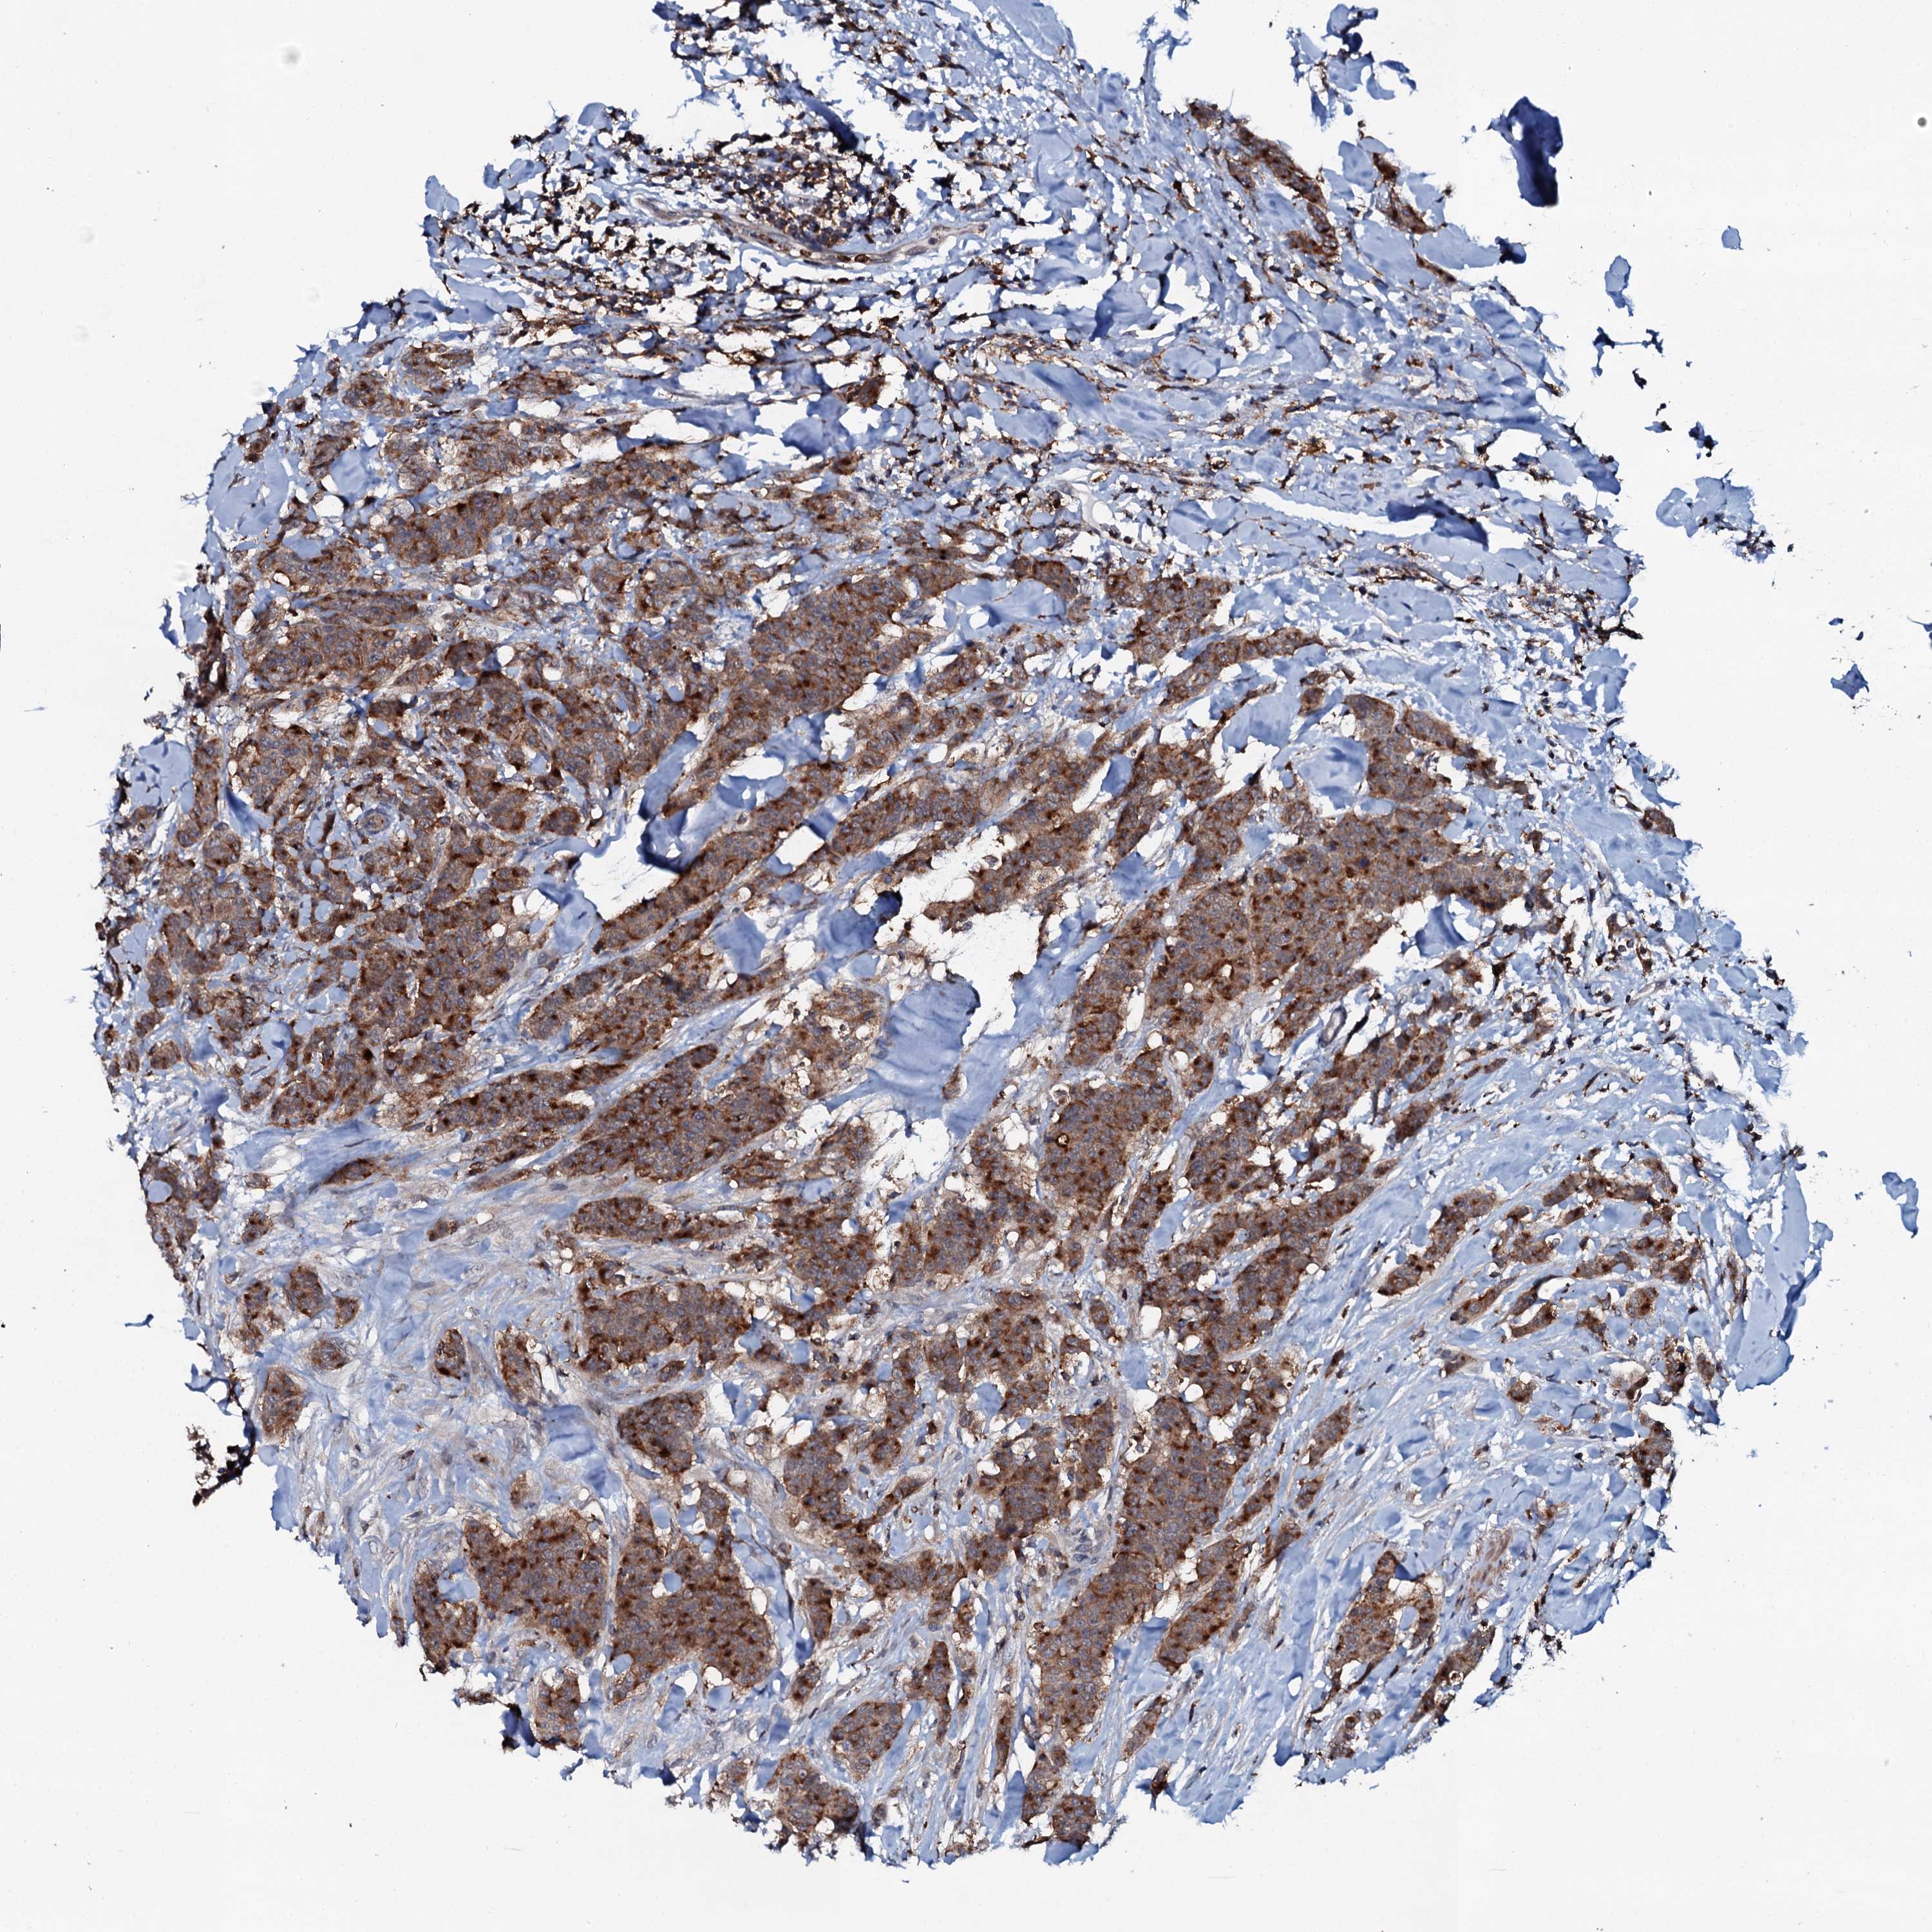

CANCER BREAST CANCER Show tissue menu

BRCA TCGA BRCA VALIDATION PROTEIN EXPRESSION